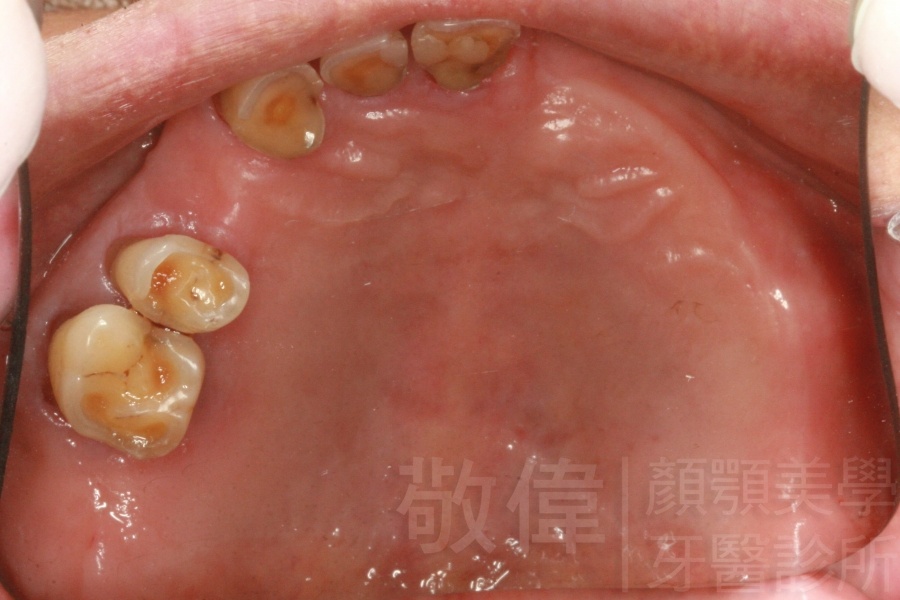

治療前-缺上排前牙   治療後